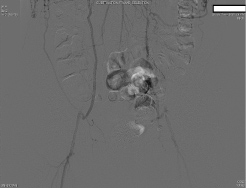

Preoperatively, the surgery service was queried by the anesthesiologist as to whether the routes of collateralization to the lower extremities were known. The response indicated that there had been intraabdominal collaterals demonstrated on angiography from the radial artery catheterization upon admission. The patient was then transported to the operating room, and a radial arterial line was placed during preoxygenation and prior to induction. After further consideration, the surgeon requested a delay of induction of anesthesia for further angiography review. Upon examination, a large right inferior epigastric artery was noted on the preoperative catheterization films, suggesting that collateral blood from the right internal mammary artery may supply the right lower extremity. The origin of collateral flow, however, could not be determined. Existing angiography was also unable to clearly demonstrate the collateral blood flow to the left lower extremity. At this point, the case was aborted before induction of anesthesia, and further angiography studies were ordered in consultation with a vascular surgeon. A subsequent aortogram and angiography of the internal mammary arteries demonstrated that collateral flow to the lower extremities was dependent on both the left and right internal mammary arteries (Figure 1, Figure 2 and Figure 3). Gastroepiploic artery was not considered as an alternative to the LIMA because of lack of institutional experience with the procedure.

Figure 1: Angiogram demonstrating infrarenal aortic occlusion with collateralization.